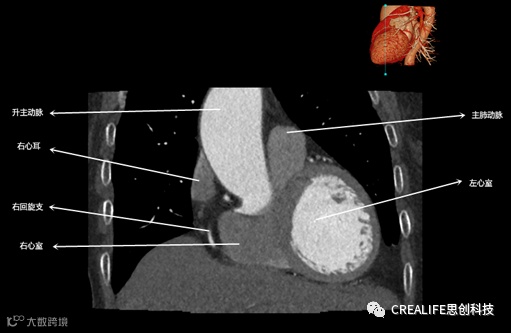

今天,跟大家分享心脏影像的经典层面——冠状位。通过冠状位的影像,我们可以从正位观察到心脏结构,看到主动脉的纵向剖面及冠窦交界处的心脏形态等多方位的心脏结构。现在,就让我们率先一睹“冠状位”的奇妙风采吧!